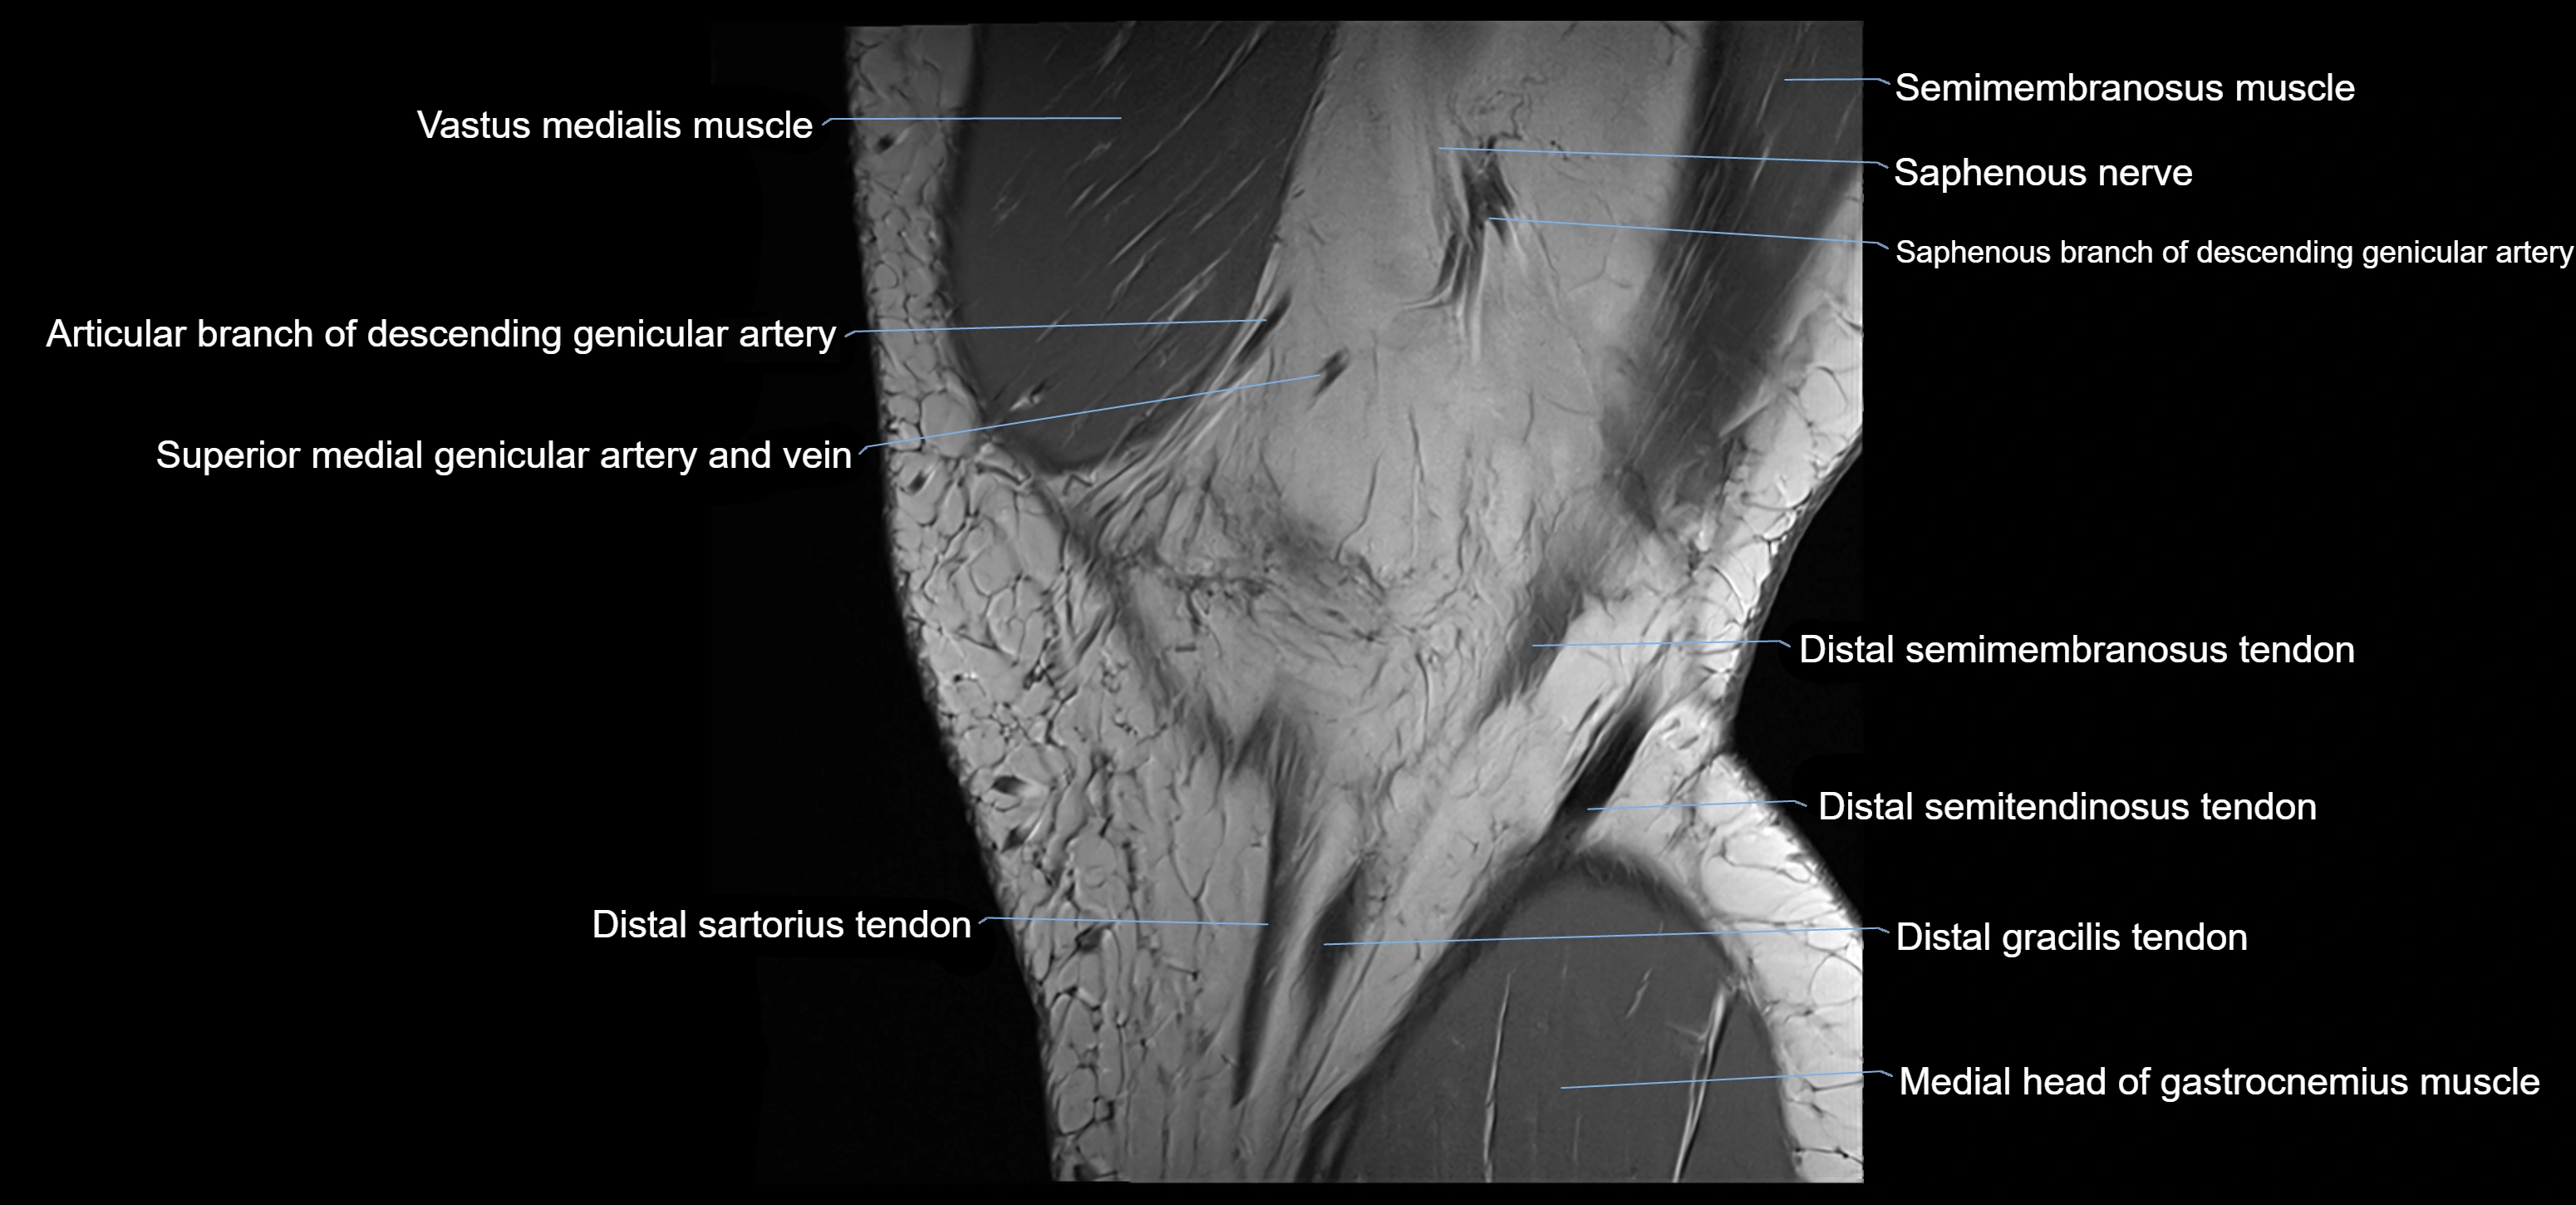

- Descending genicular artery (Articular branches)

- Descending genicular artery (Saphenous branch)

- Distal semimembranosus tendon

- Distal semitendinosus tendon

- Gracilis tendon (Distal)

- Medial head of gastrocnemius muscle

- Saphenous nerve

- Sartorius tendon (Distal)

- Semimembranosus muscle

- Superior medial genicular artery

- Superior medial genicular vein